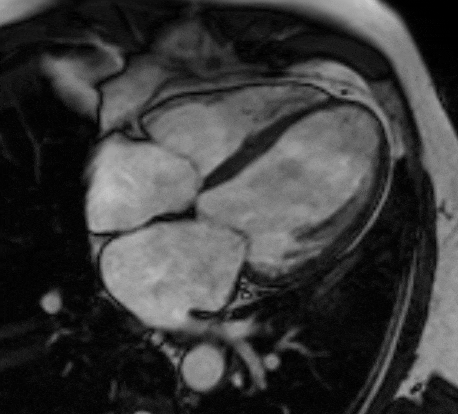

MRI Scans

MRI remains a highly specialized area within teleradiology, with relatively few radiologists possessing advanced expertise in its interpretation. At our institution, MRI studies are reported by highly qualified radiologists trained at leading institutes in India and internationally, each with dedicated subspecialty experience. We provide comprehensive reporting across all major MRI domains, including Neuroradiology, Head and Neck, Musculoskeletal, Thoracic, Abdominopelvic, and Breast imaging, while maintaining consistently high standards of accuracy, quality, and clinical reliability.

Brain & Spine MSK Cardiac MRI Breast MRI MR Angiography Pelvic